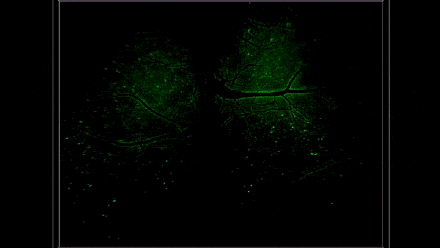

9月13日,@清华大学 戴琼海团队宣布新一代介观活体显微仪器RUSH3D问世。这个成果填补了当前国际范围内对哺乳动物介观尺度活体三维观测的空白,为揭示神经、肿瘤、免疫新现象和新机理提供了新的“杀手锏”。